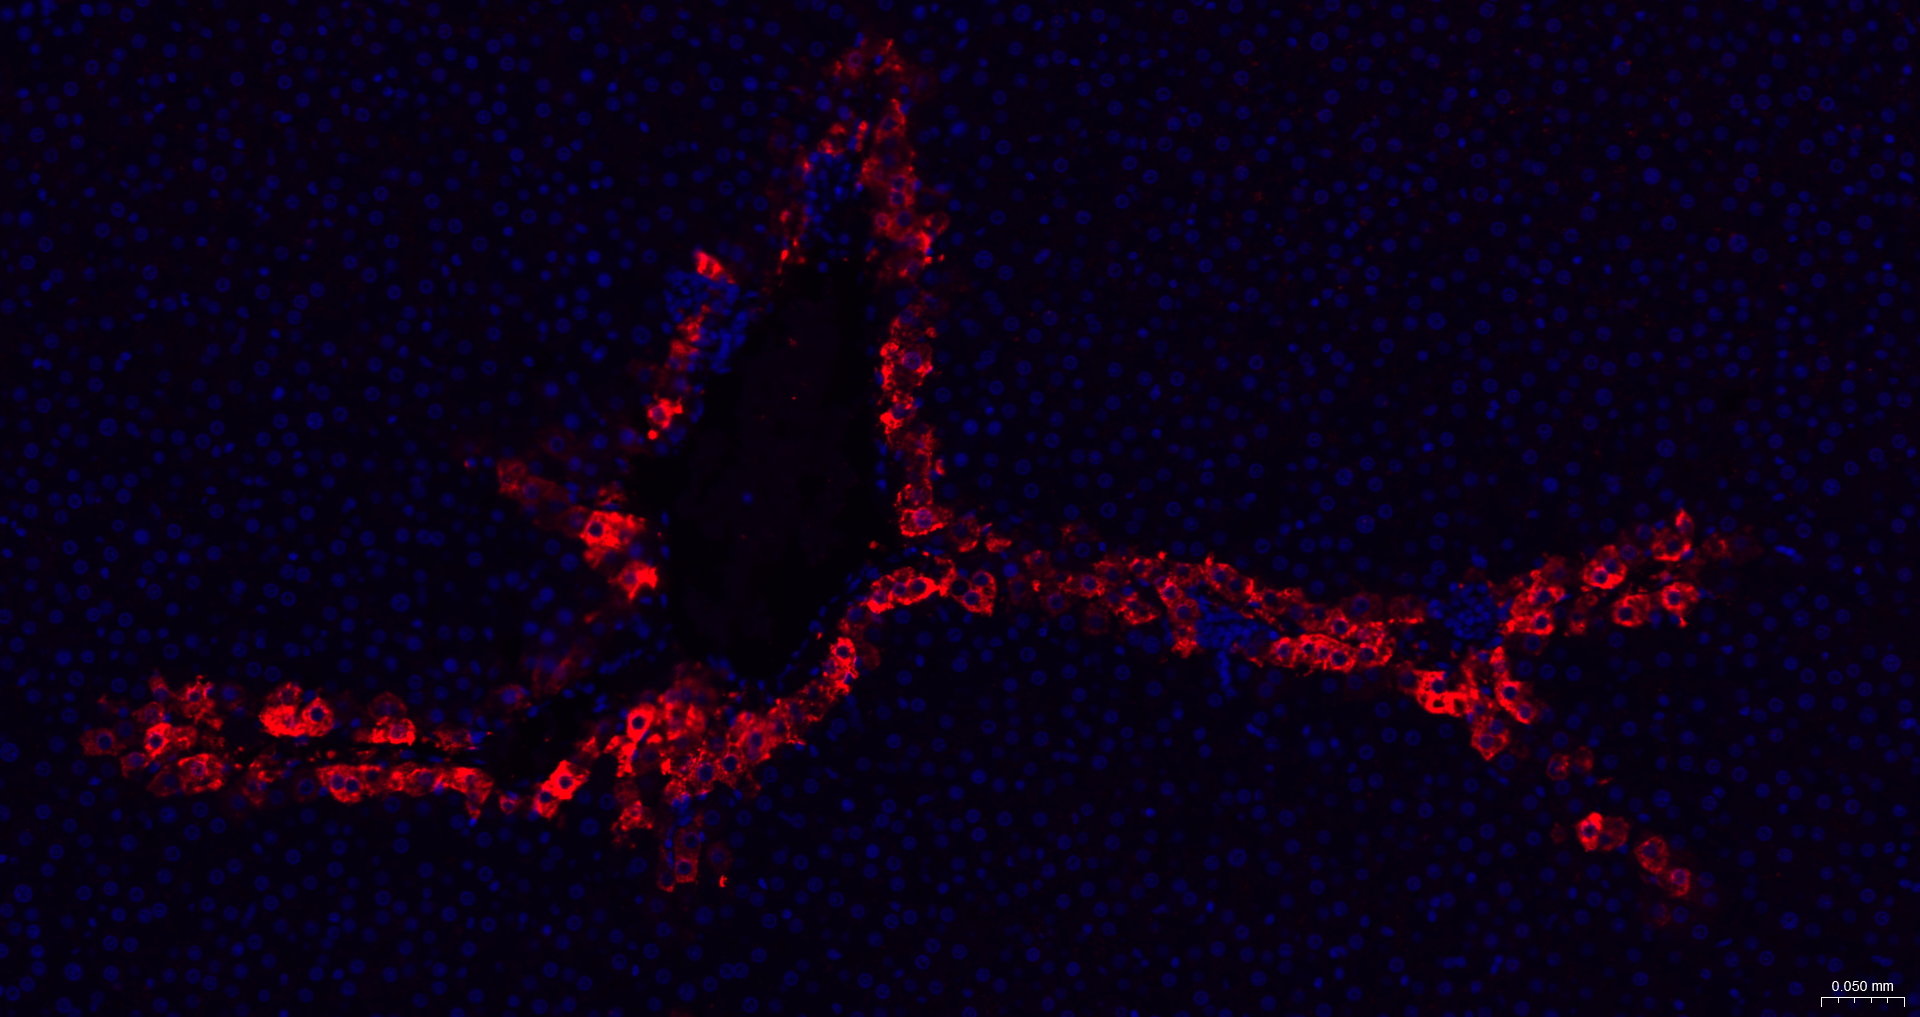

• IHC-P

• IF(IHC-P)

IHC-P IHC-P1:50-200

IF(IHC-P) IFIHC-P1:50-200